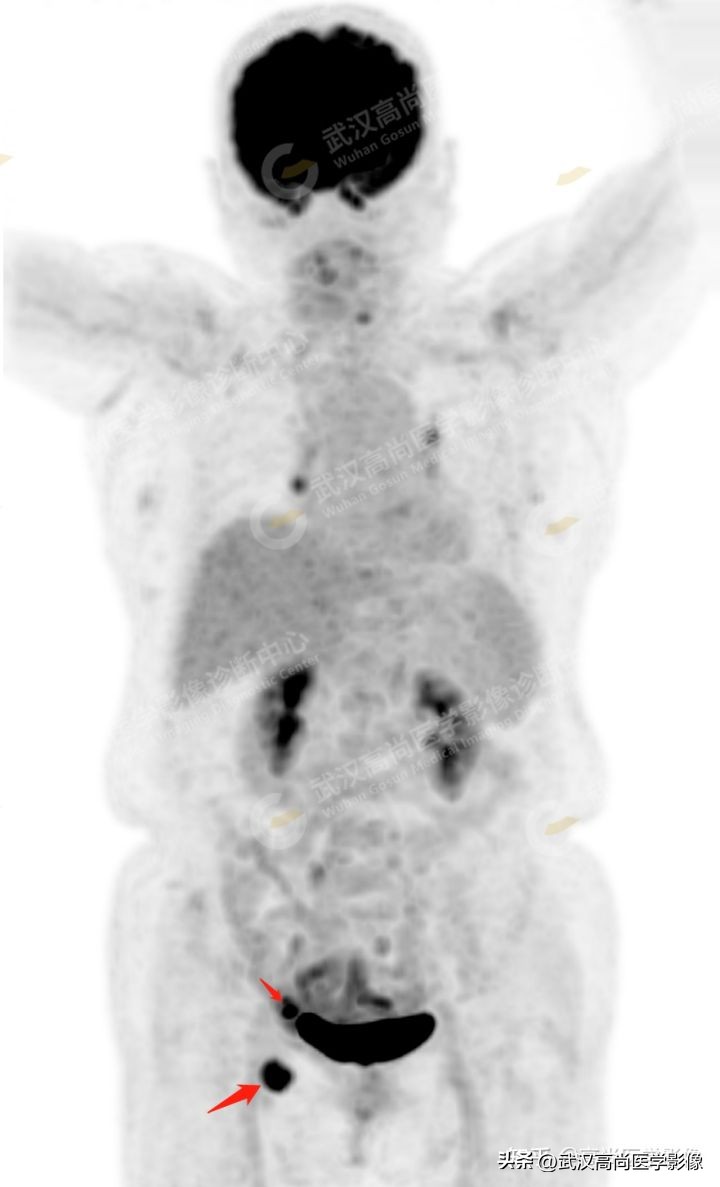

本院PET/CT检查:

1. 右侧髂血管旁及腹股沟多发高代谢增大淋巴结,腹膜反折处高代谢病灶,均考虑为转移。

2. 右侧附件区囊性低密度灶,代谢减低,多考虑为良性病变(囊肿)。

1、 常规全身PET/CT检查范围内未见明显高代谢原发灶,考虑有无可能是下肢皮肤癌转移,故查看询问双下肢是否有黑痣且加扫双下肢,但仍未发现可能的原发病灶。

2、 右侧附件囊性病变,体积小,密度均匀,边界较清楚,囊壁光滑均匀,代谢减低,无明显囊壁厚薄不均、壁结节、线性分隔、实性成分、边界不清及代谢增高等表现,亦无明显腹水征象,结合年龄及绝经史,综合考虑为良性病变(囊肿可能)。